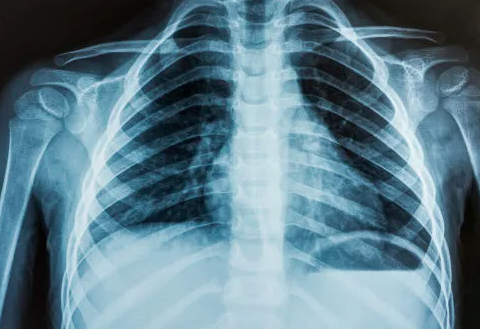

Uma situação inusitada e preocupante chamou atenção nas redes sociais, após um exame identificar um objeto estranho no ânus de um homem, que teria procurado atendimento médico, após três dias de prisão de ventre, inchaço abdominal e fortes dores.

Raio-X identificou objeto estranho em corpo de homem por Reprodução

De acordo com a equipe que o atendeu, um exame de raio-X revelou que havia uma xícara de cerâmica alojada dentro do intestino do paciente, que não conseguia evacuar. O homem foi atendido no Hospital Geral Dajia Li, em Taichung, Taiwan.

A peça, com cerca de 6 centímetros de largura e 8 de altura, tinha a superfície lisa, o que dificultou as primeiras tentativas de remoção. Médicos ainda usaram instrumentos específicos para tentar puxá-la, mas não tiveram sucesso.

De acordo com a imprensa local, o médico relatou que o paciente ficou constrangido com a situação e evitou explicar como o objeto foi parar na região. “Inacreditável, até eu fiquei chocado quando vi”, afirmou Dr. Wu Kunda.

O homem teria declarado que “não sabia” e que “foi um acidente”. Ele ainda admitiu ter tentado expulsar o objeto por conta própria antes de buscar ajuda. Com parte do intestino com sinais de comprometimento do fluxo sanguíneo, a equipe concluiu que a única saída seria recorrer a uma cirurgia de emergência sob anestesia geral. O procedimento durou cerca de duas horas.

O Dr. Wu e sua equipe abriram o abdômen do paciente, retiraram a xícara e realizaram uma colostomia temporária para permitir que ele conseguisse evacuar durante a recuperação.